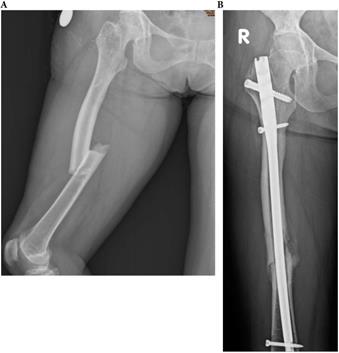

Figure 4

A 71-year-old female patients with type 4 OI had right midshaft femoral fracture with intramedullary nailing treatment in November 2014, which resulted in union. (a) Pre-operation fracture picture (b) Follow up in May 2016.

Int J Med Sci Image

Influence of treatment on healing rate

In OI type 4, 2 of 5 (40.0%) fractures resulted in non-union. All two patients with type 4 OI who were conservatively treated with OI had shaft fractures resulting in non-unions. Three other patients with type 4 were surgically treated for shaft fractures. All resulted in union (2 IN, 1 PF) (Figures 3, 4, 5). In patients with OI with type 1 OI, 1 of 4 (25.0%) fractures resulted in non-union (Figure 6), for type 3, 1 of 6 (16.7%) fractures resulted in non-union (Figure 7).

Overviewing all shaft fractures (n=9), intramedullary fixated fractures resulted in one non-union of three fractures (33.3%). Plate-fixated fractures resulted in one non-union of three fractures (33.3%). Conservatively treated shaft fractures resulted in two non-unions of three fractures (66.6%).